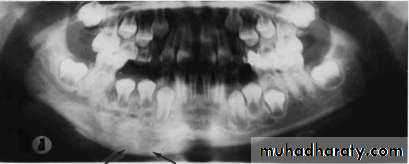

• CHRONIC SUPPURATIVE OSTEOMYELITIS

• RADIOLOGY

• Patchy, ragged & ill defined radiolucency. Often contains radiopaque sequestra.• Sequestra lying close to the peripheral sclerosis & lower border.

• New bone formation is• evident below lower border.